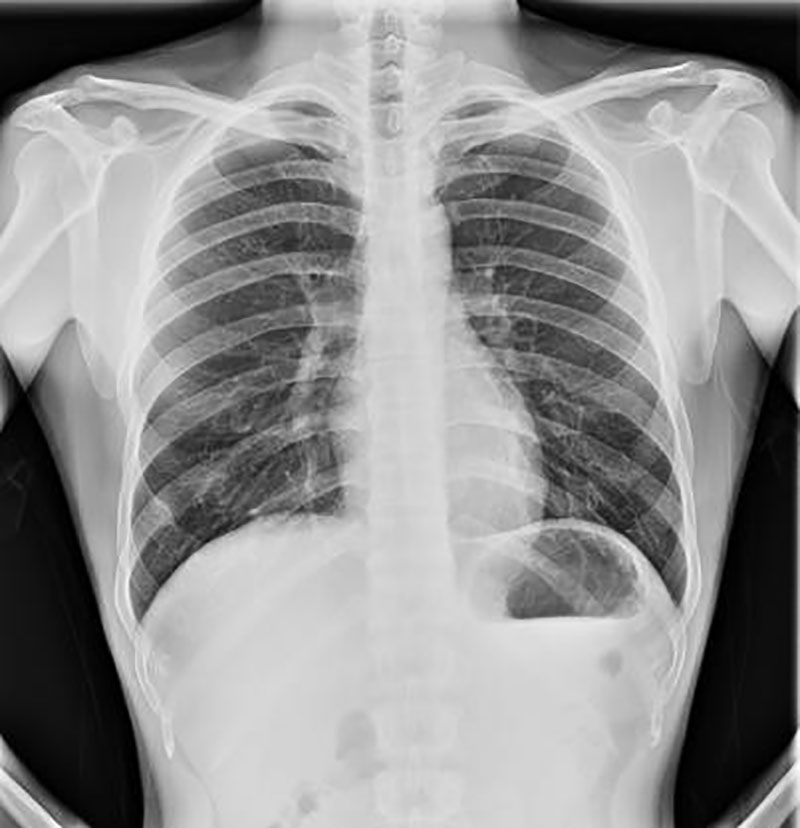

大通V90體檢車醫療車,各工位內外對講逆變電系統,帶充電功能。受檢者進出的門,門內嵌有不低于L5-2mm 的鉛板,門的 四邊與門框均有重疊交叉的鉛板,門開著時,保障射線沒有折射泄漏。達到國標GBZ130-2013《醫用X 射線診斷衛生防護標準》和 GBZ264-2015《車載式醫用 X 射線診斷系統的放射防 護需求需求》,射線泄漏 W2. 5uSV/H,醫務人員工作處 W 1uSV/H提供環?;蛘咝l監部門的《射線檢測報告》。專門針對人眼視覺工程的 LUT 設計,更符合人眼觀察,降低閱片對眼睛的負擔,降少技師勞動強度。車內裝有空調,制冷量 3000,制熱量 3000,制冷制熱效果都很不錯。

新款最新大通V90體檢車醫療車實拍圖_推薦車型-現車,有利于指揮中心和接種人員隨時了解現場情況。該車配備齊全,保證整個接種過程有利于、安全、穩當。市民能夠安全地在機動車身上接種疫苗。在主動安全方面,V90是第一款配備ADAS智能駕駛輔助系統,包括ACC自適應巡航系統、AEB自動制動系統等功能,智能駕駛輔助已達到L2級。先進的影像鏈,圖像優秀,高頻高壓發生器。關鍵部件裝減震緩沖裝置。